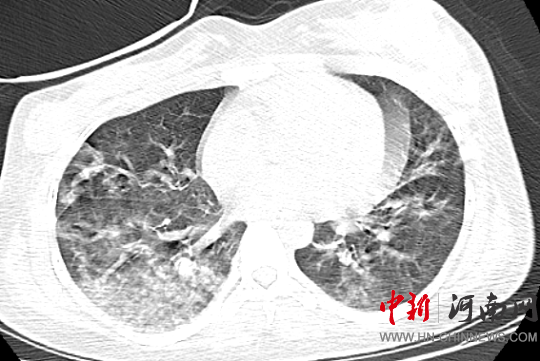

經(jīng)過VV-ECMO

床旁CRRT(血液凈化治療)

抗病毒

抗感染等治療

霖霖的情況好轉(zhuǎn)

肺部感染明顯改善